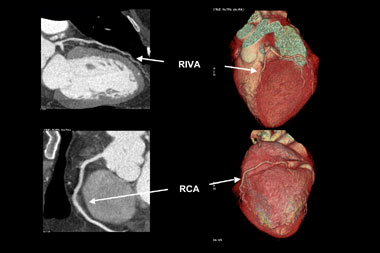

In den letzten Jahren hat die Computertomographie das Magnetresonanz-Imaging (MRI) im Bereich der Herzkranzgefässe überholt. Durch die rasante Entwicklung immer schneller werdender Geräte, welche ursprünglich langsam Schicht um Schicht, bald aber 4, 16, 32 und seit kurzem bereits 64 Schichten gleichzeitig erfassen, wurde es möglich innert kürzester Zeit – allerdings mit erheblicher Strahlenbelastung - die Herzkranzgefässe mit bisher ungeahnter Genauigkeit darzustellen (Abbildung 1). Die Herzkranzgefässe lassen sich hiermit in ihrer gesamten Länge neben dem kardialen Bereich vollständig verfolgen und Einengungen können in vielen Fällen erkannt werden. Zudem bietet die Computertomographie die Möglichkeit der Quantifizierung von Kalziumablagerungen in der Gefässwand wie sie für die Arteriosklerose typisch sind («Gefässverkalkung») – Kalk ist Ausdruck für das Ausmass des arteriosklerotischen Prozesses. Entsprechend wurde von verschiedenen Forschungsgruppen ein eigentliches Kalzium-Score entwickelt, welches ähnlich wie die kardiovaskulären Risikofaktoren prognostische Hinweise liefern soll.

Abbildung 1: Darstellung von multiplanar rekonstruierten (MPR, links) und dreidimensional (3D-volume rendered) Bilder eines Patienten mit normalen Koronararterien. Ramus interventrikularis anterior (RIVA) und rechte Koronararterie (RCA)